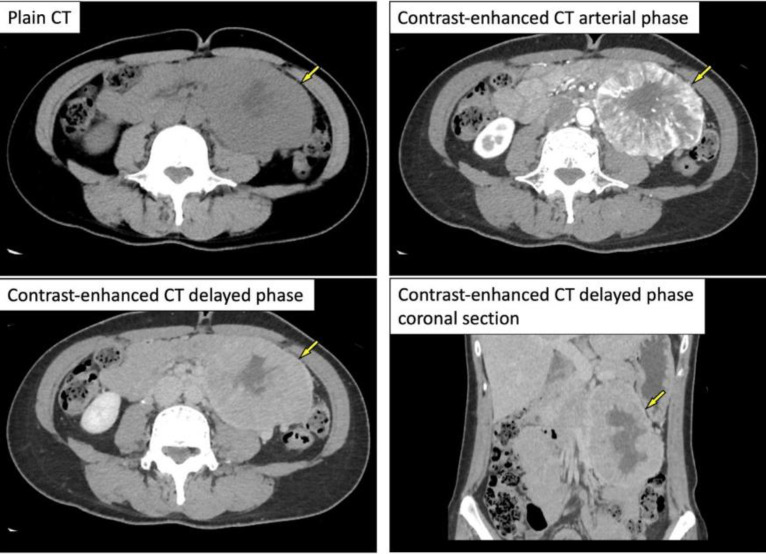

一名 50 岁的妇女经全身体检被诊断为缺铁性贫血。对比增强腹部 CT 和磁共振成像显示,腹膜后间隙有一个巨大的高血管肿块,内部变性坏死。她被转到我院接受进一步评估和治疗。由于副神经节瘤是最有可能的影像学诊断,因此对她进行了 123I-MIBG 闪烁扫描。结果显示,腹膜后病变处有明显的异常积聚,提示为副神经节瘤,未发现其他异常积聚。血浆中的几种儿茶酚胺及其尿液代谢物均正常。在随后的 18F-FDG PET/CT 检查中,发现腹膜后病灶有较高的 FDG 摄取(SUVmax=38)。右肺下叶底部的一个小结节也发现了 FDG 摄取(SUVmax= 9.8)。对比增强成像显示右肺底部有一个高血管结节,提示副神经节瘤肺转移。切除了腹部病灶和右肺结节,根据病理结果诊断为腹膜后副神经节瘤和肺转移。在该病例中,18F-FDG PET/CT 在寻找副神经节瘤转移灶方面发挥了作用。我们报告了 123I-MIBG 在副神经节瘤中的蓄积与 18F-FDG 摄取之间的关系,并回顾了相关文献。

A 50-year-old woman was diagnosed with iron deficiency anemia on general medical examination. Further, contrast-enhanced abdominal CT and magnetic resonance imaging revealed a large hypervascular mass with internal degeneration and necrosis in the retroperitoneal space. She was referred to our hospital for further evaluation and treatment. Because the paraganglioma was most likely as the imaging diagnosis, 123I-MIBG scintigraphy was performed. It revealed the marked abnormal accumulation in the retroperitoneal lesion indicating the paraganglioma and no other abnormal accumulation was noted. Several plasma catecholamines and their urinary metabolites were normal. On the subsequent 18F-FDG PET/CT, high FDG uptake was found in the retroperitoneal lesion (SUVmax=38). FDG uptake was also found in a small nodule at the base of the lower lobe of the right lung (SUVmax= 9.8). Contrast-enhanced imaging revealed a hypervascular nodule at the base of the right lung, suggesting pulmonary metastasis of a paraganglioma. The abdominal lesion and right lung nodule were excised, and retroperitoneal paraganglioma and pulmonary metastasis were diagnosed based on the pathology findings. In this case, 18F-FDG PET/CT was useful in the search for paraganglioma metastasis. We report a relationship between 123I-MIBG accumulation and 18F-FDG uptake in paraganglioma and review the relevant literature.